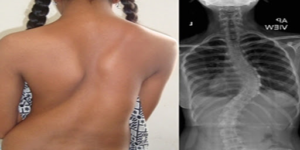

Skolyoz nedir? – 2

Skolyoz tedavisi; hastaların yaşı, eğriliğin derecesi ve yeri, yetişkinlerde ağrıların şiddeti, fiziksel muayene ve görüntüleme yöntemleri bulguları, eğrilik derecesinde zaman içinde görülen artış gibi nedenler göz önünde bulundurularak ve kişiselleştirilerek planlanmaktadır. Skolyoz röntgeni ve muayene sayesinde konan erken tanı, skolyoz tedavisinin başarısını oldukça artırmaktadır.

Skolyozun tedavisinde gözlem, korse tedavisi, fizik tedavi ve cerrahi operasyon uygulanmaktadır. Tedavinin ilk seçeneği olan gözlem genellikle 20 derecenin altındaki eğriliklerde uygulanmakta ve zaman içinde eğriliğin ne kadar arttığını göstermektedir. Skolyoz fizik tedavi uygulamaları ve cerrahi operasyon özellikle yetişkinler ve daha şiddetli vakalar için uygundur. Bununla birlikte hem çocuklarda hem de yetişkinlerde skolyoz tedavisi için en son olarak cerrahi operasyonlara başvurulmaktadır.